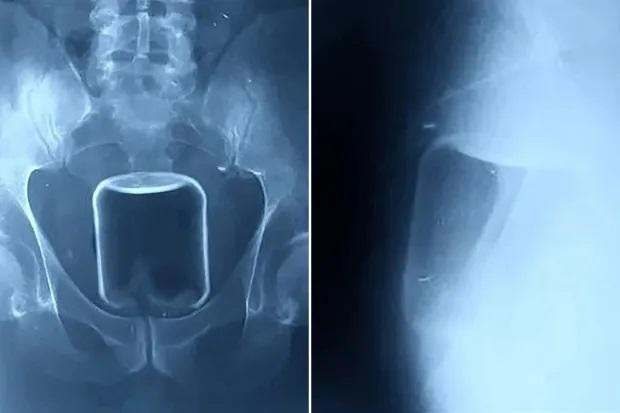

從報道顯示的X光片看見,體積不細的玻璃瓶在肛門內較高位置,醫生最後成功取出它,連帶一個安全套。報道稱,那男子將一個容量500毫升的玻璃瓶塞進肛門,並將其推進腸道,最後因無法取出而求醫。俄羅斯下諾夫哥羅德一間醫院公開有關個案,稱醫生非道德警察,不會評論病人非傳統的性傾向,呼籲民眾若遇相同情況,須尋求醫療協助。